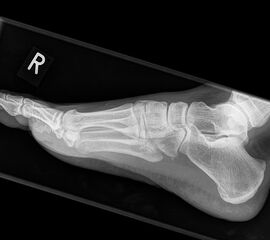

Fuß seitlich ohne Belastung

Positionierung:

• Patient befindet sich in Seitenlage auf dem Röntgentisch, der zu untersuchende Fuß befindet sich unten.

• Der Fuß liegt seitlich auf der Röntgenkassette.

• Der Zentralstrahl fokussiert auf das Kalkaneokuboidalgelenk knapp cranial der Basis des Os metatarsale V.

• Die Röhre ist mit 0° vertikal eingestellt.

Kennzeichen des Röntgenbildes:

• Immer wenn die Tibia nicht zentral über dem Talus steht, handelt es sich um unbelastete Aufnahmen.

Besondere Bemerkungen zum Beispielbild:

• Der Patient erlitt ein Mittelfußtrauma. Unter Frakturverdacht erfolgten die unbelasteten Aufnahmen.

• Die Frakturlinie im Os cuneiforme I ist in der lateralen Aufnahme schwer erkennbar.

• Unauffällige Abbildung des restlichen Fußskeletts.

• Für die OP-Planung erfolgte dann noch ein Schnittbildverfahren.

Zur Vollansicht und zum Lesen der Bildbeschreibung bitte die Bilder anklicken.